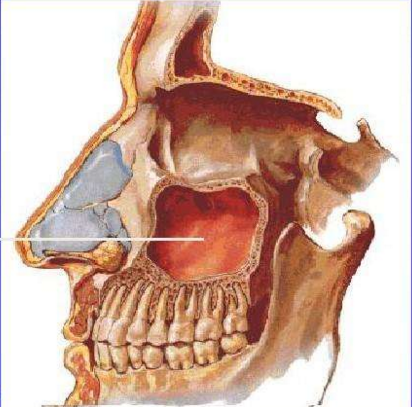

牙齿的根部与上颌窦的下壁相邻,当牙齿的感染向上扩散,可以到达上颌窦内。而牙齿的感染往往伴有厌氧菌。厌氧菌在鼻窦内这个相对密闭缺氧的空间内会如鱼得水,会迅速的繁殖。厌氧菌感染往往伴有恶臭味。